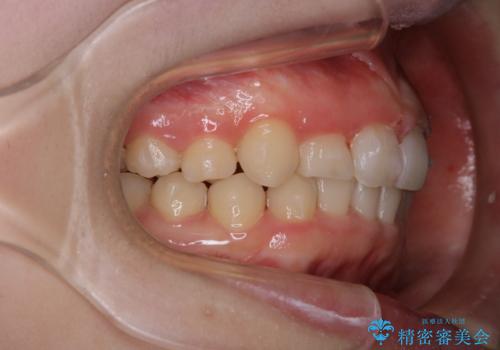

- インビザラインでのマウスピース矯正中の方で、歯の表面のステインをきれいに取りたいとのことでした。PMTC60分コースを行いました。

PMTC(保険外治療)は、毎日の歯磨きで落としきれない汚れや、コーヒ、紅茶・タバコのヤニなどの着色も除去します。目には見えない歯と歯の間・歯肉の境目・インビザライン中はアタッチメント周囲などに残っているプラーク(歯垢)もしっかり取り除きます。PMTCでは専門的な機械や材料を使用して、徹底的に汚れを除去するため、虫歯・歯周病・口臭予防などにつながります。